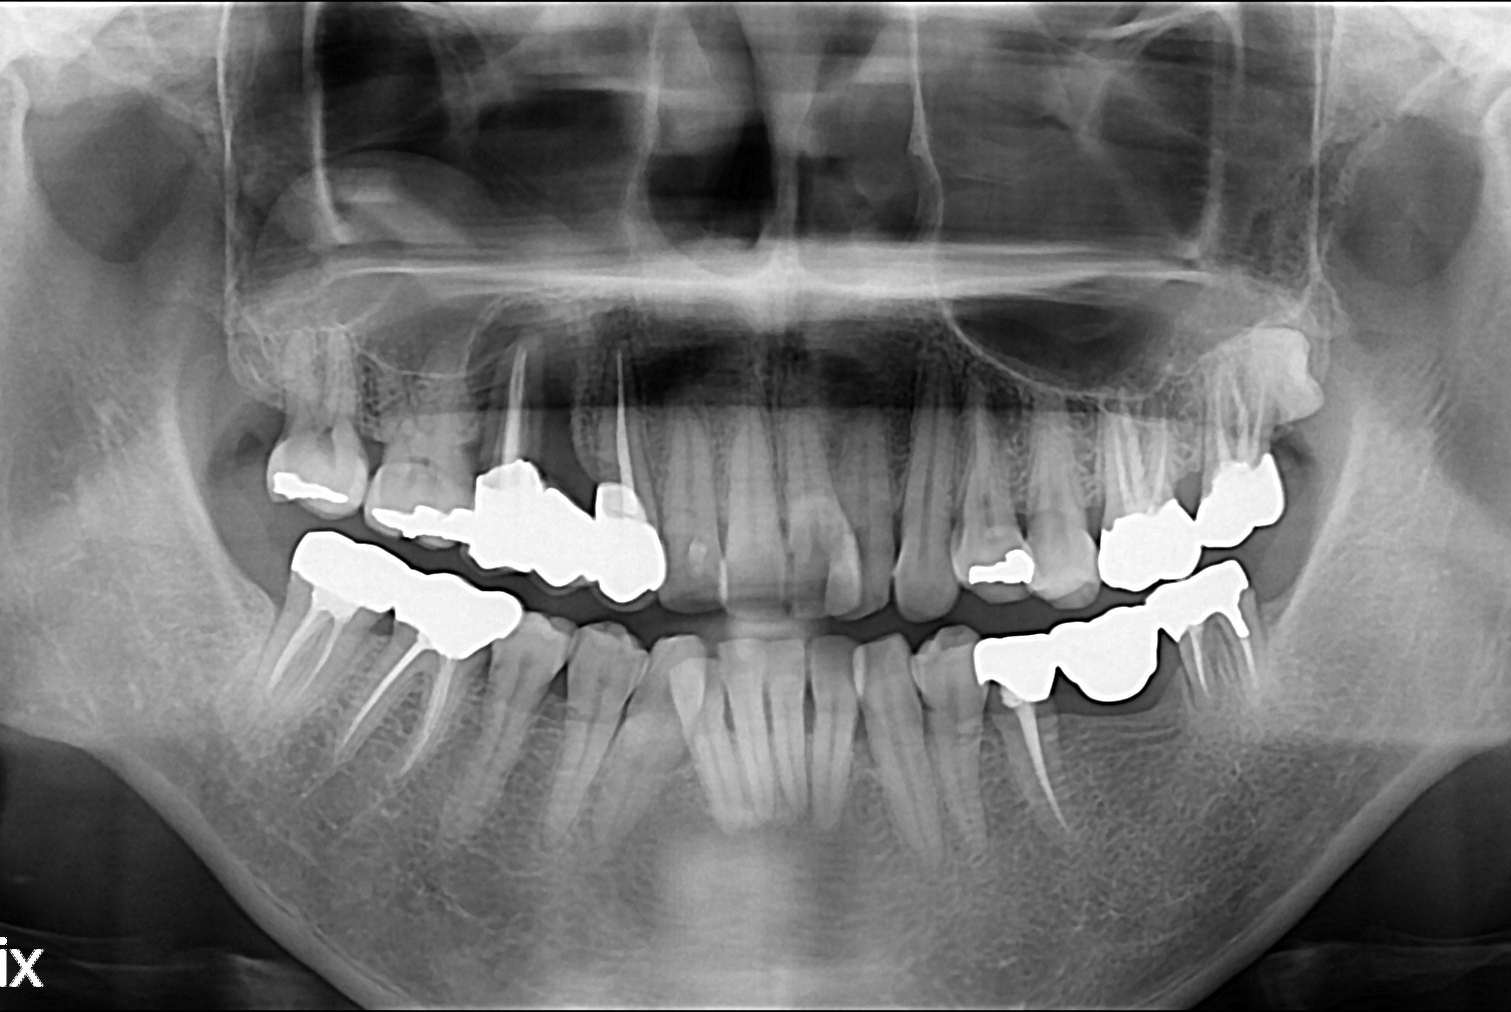

치료전 : 2019-01-17

세종치과는 많은 환자와 다양한 케이스를 바탕으로 항상 편안한 임플란트 수술을 제공하고자 노력하고,

오래동안 튼튼히 쓸 수 있는 임플란트 수술을 가장 큰 목표로 삼고 있습니다